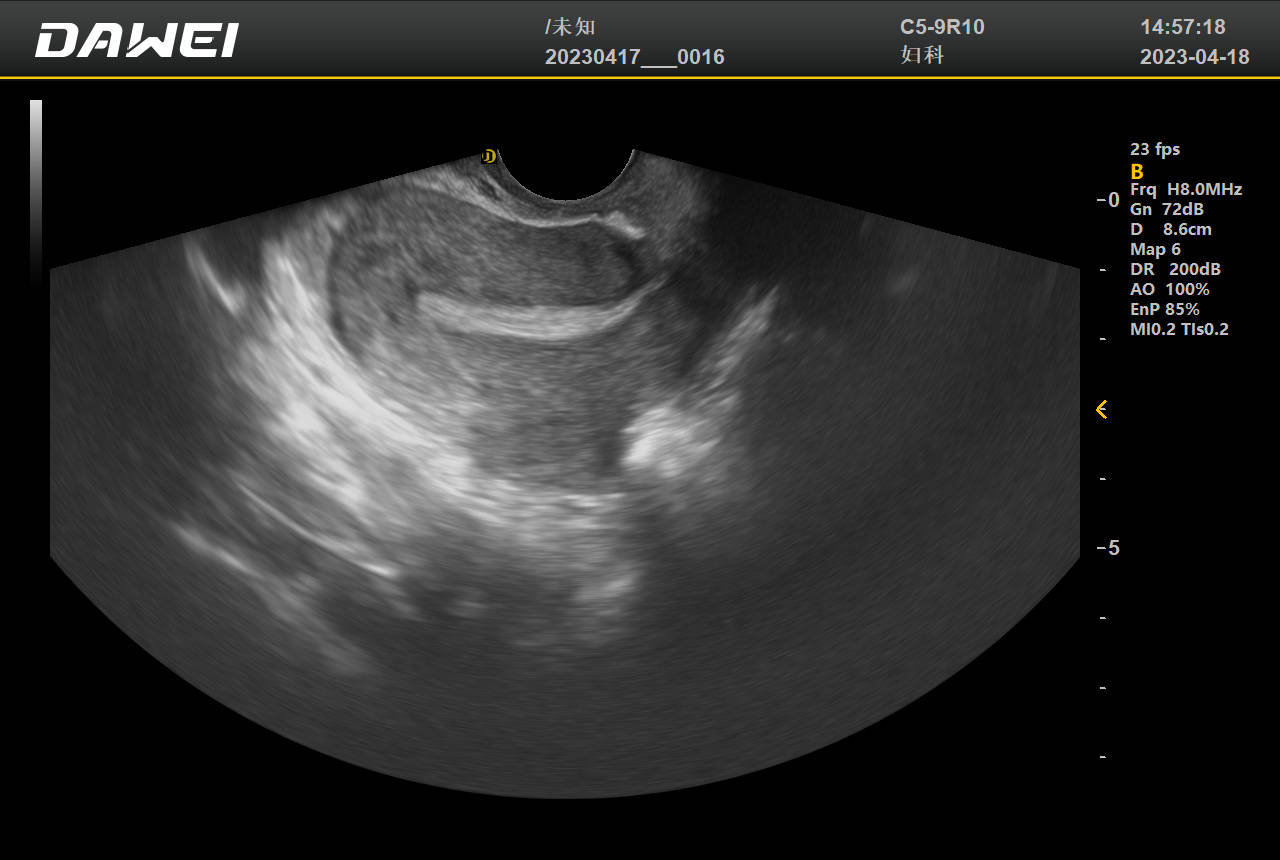

腔内彩色多普勒超声检查主要用于评估盆腔及邻近器官的结构与血流状态,具体检查内容包括以下方面1 子宫及附件检查通过经阴道或经直肠途径,可清晰显示子宫肌层子宫内膜卵巢及输卵管的形态与结构例如,可检测子宫肌瘤的位置大小及血流供应,判断卵巢囊肿的性质如囊性或实性,以及输卵管积水等病变。